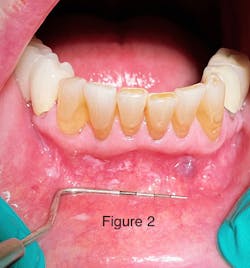

Take a look at the initial photograph. What’s the first thing that comes to your mind? Scattered, white, creamy patches in the lower anterior vestibule, each measuring approx. 3–6 mm (figure 1). Now, take a look at the second picture after the white patches were easily wiped off with gauze (figure 2). Note the red, thin membraned tissue? It was very tender to the touch.This diagnosis should be a slam dunk by now. Yup, you guessed it. Good ol’ pseudomembranous candidiasis, aka thrush.

- Acute pseudomembranous candidiasis consists of creamy, loose patches of desquamative epithelium that are easily removed.1 Red tissue tender to the touch is what is painful to the patient.